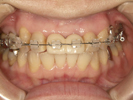

30代女性

事故のため、前歯を2本失いました。

インプラントと矯正治療をしました。

| 治療前 | ||

| インプラント後、仮歯を入れました。 | ||

| 矯正設置を着用し、歯列矯正を行いました。 | ||

| 治療後 | ||